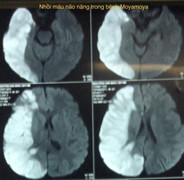

Thông tin bệnh viện Nhi đồng 2 cho biết, có hai bệnh nhi liên tục lên những cơn đau đầu, cha mẹ cho trẻ nhập viện điều trị nhưng không dứt điểm dẫn đến trẻ mang bệnh lý mạch máu não hiếm gặp.